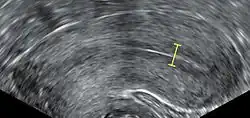

The endometrium is the innermost lining layer of the uterus, and functions to prevent adhesions between the opposed walls of the myometrium, thereby maintaining the patency of the uterine cavity.[12] During the menstrual cycle or estrous cycle, the endometrium grows to a thick, blood vessel-rich, glandular tissue layer. This represents an optimal environment for the implantation of a blastocyst upon its arrival in the uterus. The endometrium is central, echogenic (detectable using ultrasound scanners), and has an average thickness of 6.7 mm.

Thin endometrium may be defined as an endometrial thickness of less than 8 mm. It usually occurs after menopause. Treatments that can improve endometrial thickness include Vitamin E, L-arginine and sildenafil citrate.[17]

Observation of the endometrium by transvaginal ultrasonography is used when administering fertility medication, such as in in vitro fertilization. At the time of embryo transfer, it is favorable to have an endometrium of a thickness of between 7 and 14 mm with a triple-line configuration,[21] which means that the endometrium contains a hyperechoic (usually displayed as light) line in the middle surrounded by two more hypoechoic (darker) lines. A triple-line endometrium reflects the separation of the basal layer and the functional layer, and is also observed in the periovulatory period secondary to rising estradiol levels, and disappears after ovulation.[22]

Endometrial thickness is also associated with live births in IVF. The live birth rate in a normal endometrium is halved when the thickness is <5mm.[23]